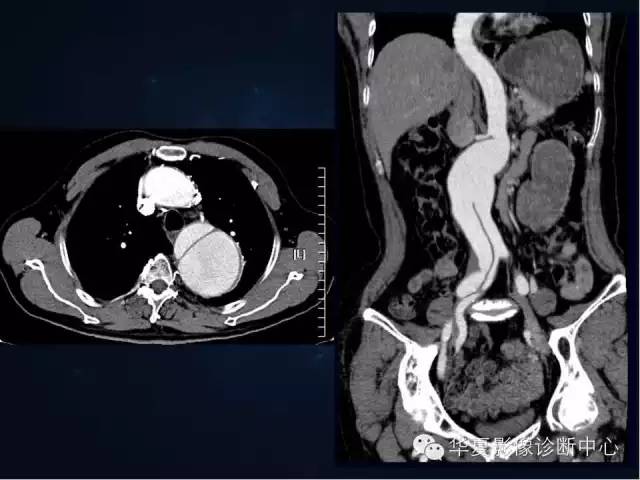

【PPT】主动脉瘤的鉴别诊断